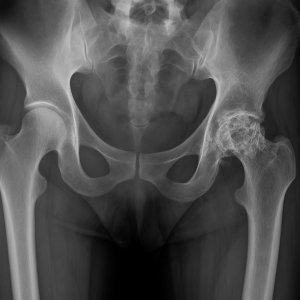

Kalça Kemiği Çürümesi Nasıl Teşhis Edilir?

Kalça kemiği çürümesi teşhisi, fiziksel muayene ve ileri görüntüleme teknikleriyle konulur:

- Fiziksel Muayene: Doktor, ağrı seviyesini, hareket açıklığını ve yürüme şeklini değerlendirir.

- Röntgen: İleri evrelerde kemik çökmesini gösterir, ancak erken evrelerde genellikle etkisizdir.

- Manyetik Rezonans (MR): Erken evrede kemik ödemini ve nekrozu tespit eden en güvenilir yöntemdir.

- Bilgisayarlı Tomografi (BT): Kemik yapısındaki değişiklikleri üç boyutlu olarak analiz eder.

Kalça Kemiği Çürümesi Hangi Evrelerde Gelişir?

Kalça kemiği çürümesi, dört farklı evrede ilerler ve her evre farklı belirtiler ve tedavi yaklaşımları gerektirir:

- Evre 1: Kan akışı azalır, ancak kemikte henüz çökme yoktur. Belirtiler çok hafiftir ve genellikle standart röntgenle tespit edilemez.

- Evre 2: Kemikte yapısal değişiklikler başlar, ancak eklem yüzeyi sağlam kalır. Manyetik rezonans (MR) görüntüleme ile teşhis edilir.

- Evre 3: Kemik yüzeyinde çökme oluşur, ağrı şiddetlenir ve hareket kısıtlılığı artar. Röntgenlerde çökme açıkça görünür hale gelir.

- Evre 4: Eklem yüzeyi tamamen bozulur, kıkırdak hasarı ve osteoartrit gelişir. Bu aşamada genellikle kalça protezi gibi ileri cerrahi müdahale gerekir.